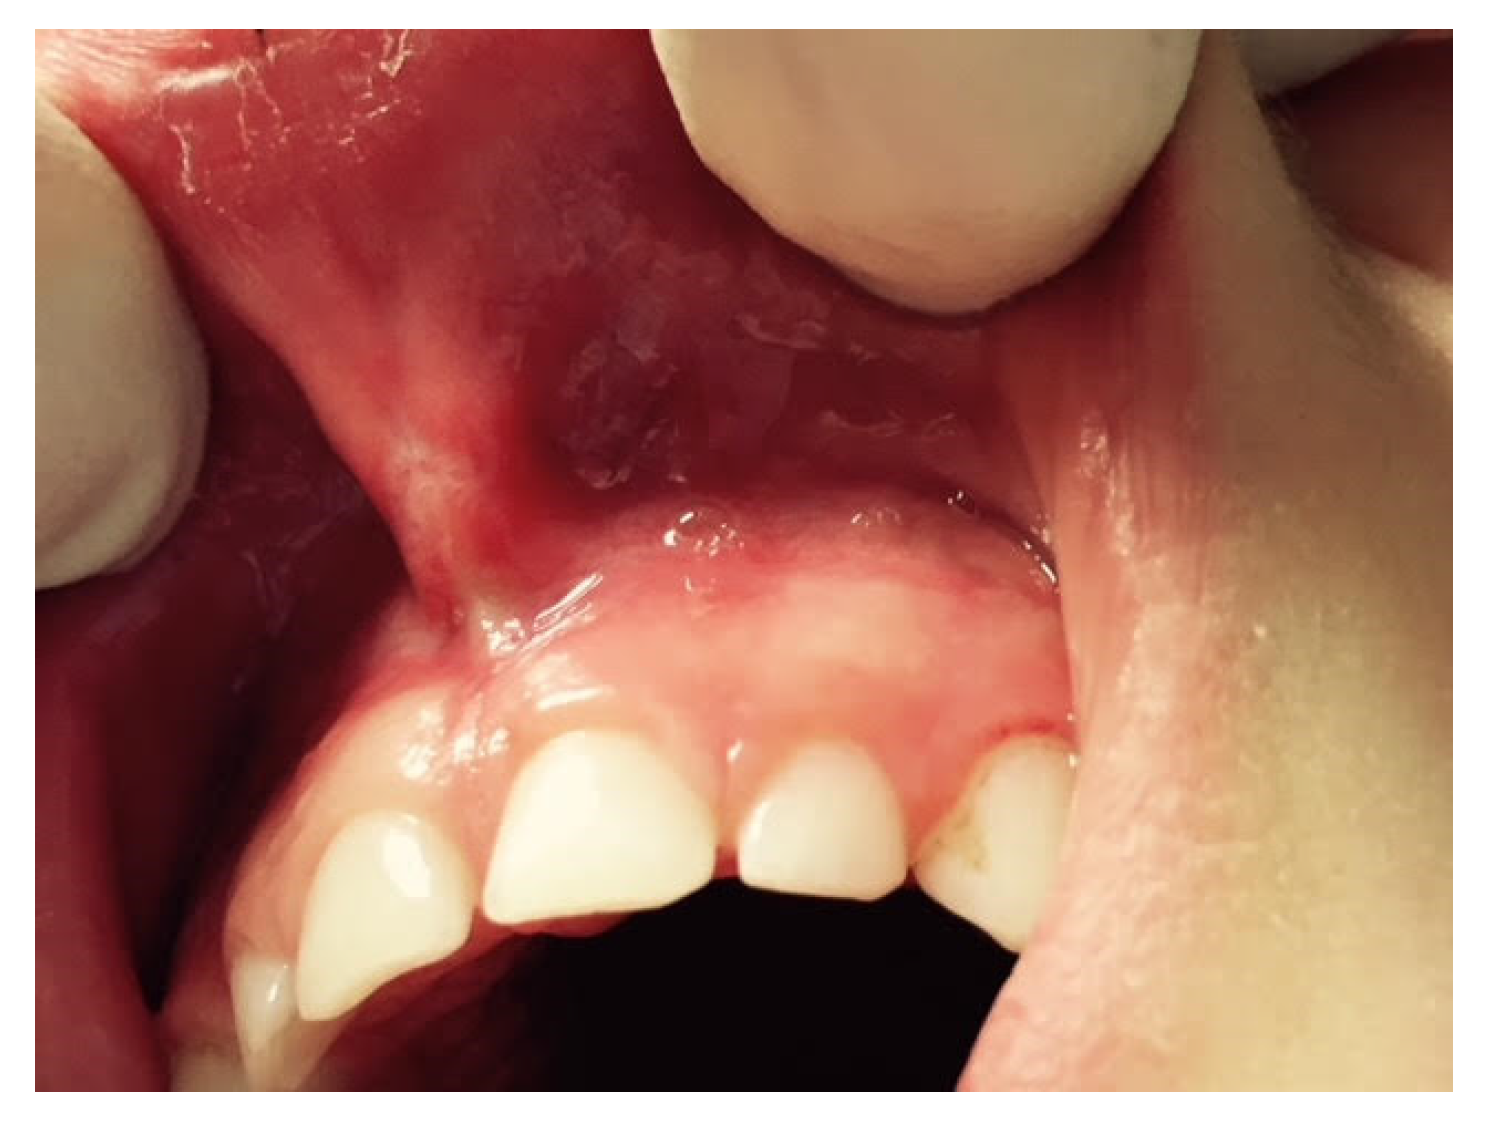

The fundamental distinction among them is the capacity to operate strictly on soft or hard tissues or both [17,18]. When just soft tissue surgery is required, the choice of the clinician must fall upon KTP, Diode, Nd:YAG or CO2 lasers [19,20]. Instead, the erbium family lasers (Er;Cr:YSGG or Er:YAG lasers) may be required when both soft and hard tissue surgery is necessary [20,21,22] (Figure 6).

Figure 6.

ULF laser surgery.

Several authors have highlighted the benefits of lasers over other types of traditional dental techniques, namely increased coagulation and hemostasis, which results in a dry surgical area for greater vision and a significantly diminished requirement for suturing (the erbium family lasers are an exception to this rule as they offer only a little haemostasis); decrease in bacteremia (tissue temperature changes brought on by laser surgery are efficient at reducing bacteria); accelerated healing process (laser beam can promote healing via photo-biomodulation); and reduced post-surgical pain [17,20,23,24,25].